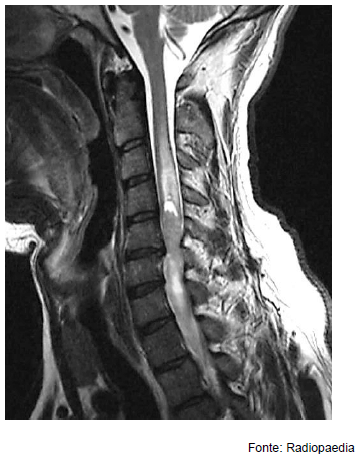

Homem, 46 anos, apresenta quadro progressivo de dor e fraqueza nos quatro membros. Foi realizada ressonância magnética da coluna cervical, cuja imagem é apresentada abaixo.

Considerando os aspectos de imagem, assinale a alternativa com o diagnóstico mais provável.